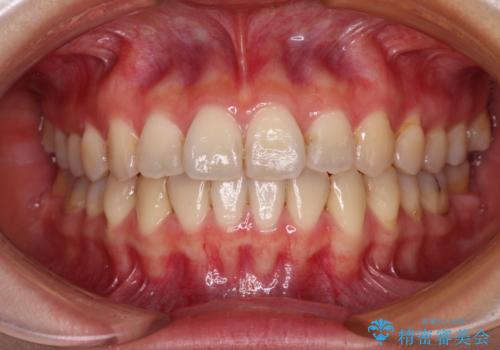

- 上顎前歯の隙間を気にして来院された患者様です。

目立たない装置を希望とのことで、インビザラインを用いて矯正治療を行うこととしました。

一度インビザラインのマウスピースセットをお渡しすると1年以上来院されず、マウスピースを破損したり紛失したりすると来院されるというのんびりとしたペースで治療を行ったため、4年間という長期にわたる治療となりました。

最終的には隙間は全て閉じ、綺麗な仕上がりとなりました。